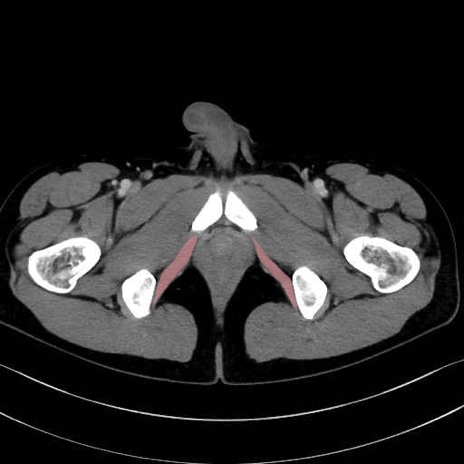

内閉鎖筋 (Obturator internus)